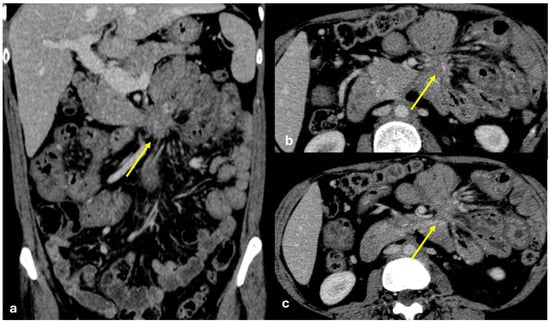

- Micro-nodular pattern: micro-nodules with a diameter ≤ 5 mm (Figure 1);

- Nodular pattern: nodules with a diameter > 5 mm (Figure 2a);

- “Omental cake”: nodular thickening of the omentum (Figure 2b);

- Plaque pattern: confluent nodular plaques, typically involving the lower surface of the right diaphragm (Figure 3);